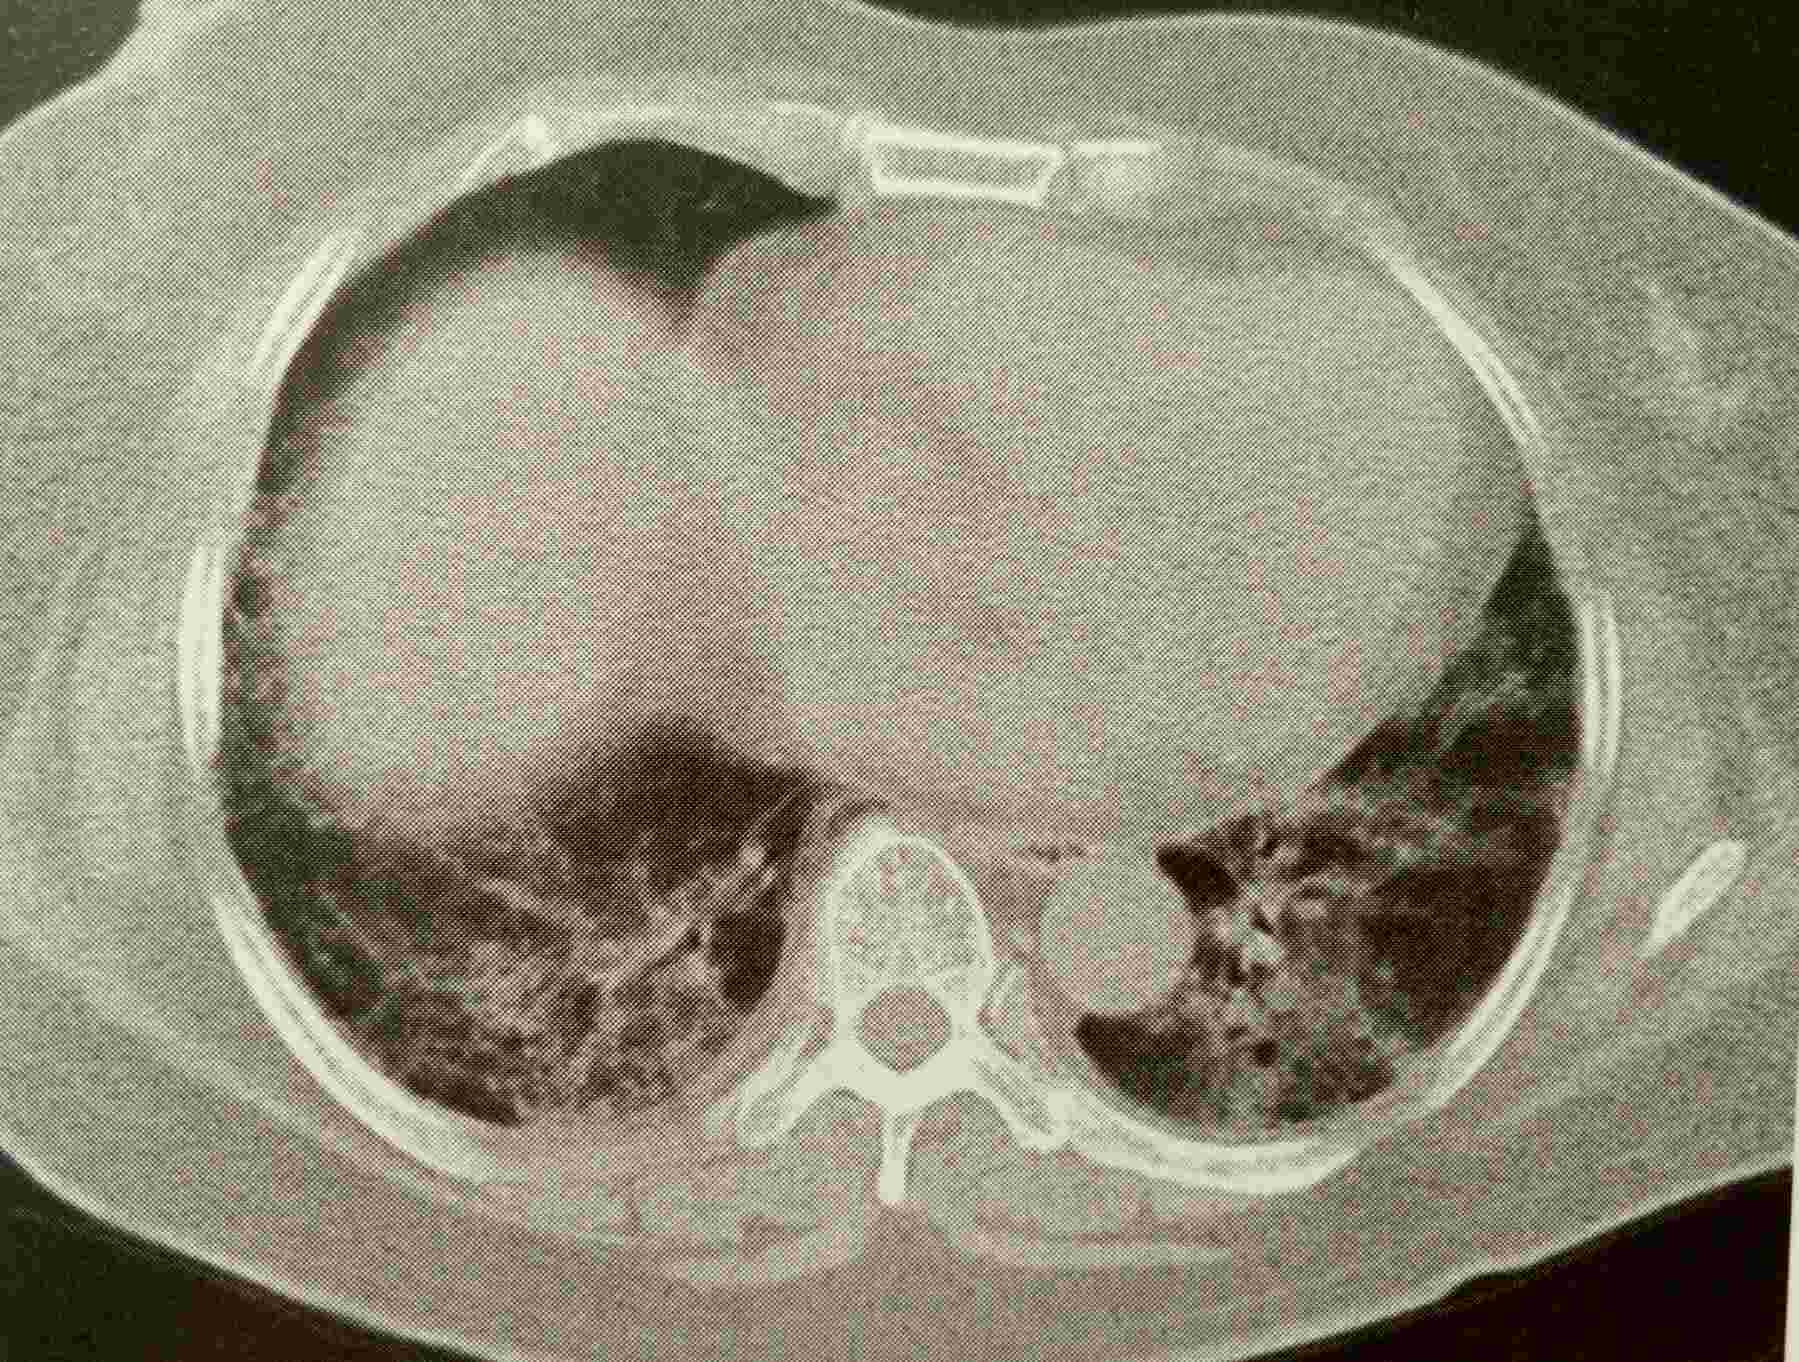

类风